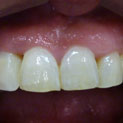

En estos casos han sido tratados con la filosofía de all-at-once, en la

misma sesión: